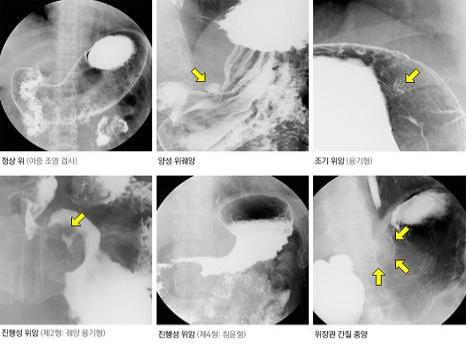

위장 조영검사로 확인할 수 있는 질환

위장 조영검사는 구조적 이상과 기능적 문제를 중심으로 평가한다.

| 위궤양·위암 의심 소견 | 궤양성 결손, 종괴 음영 |

| 위하수·위확장 | 위 위치 및 크기 이상 |

| 식도 역류 | 조영제 역류 여부 |

| 위 배출 장애 | 음식 정체 여부 |

다만 조기 위암이나 미세한 점막 병변은 발견이 어려울 수 있다.